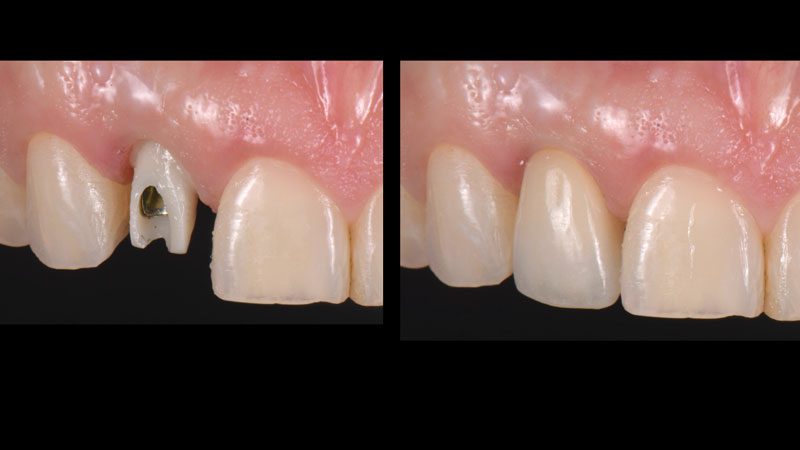

Hình 14. Thiết kế abutment cá nhân bằng zirconia, mão sứ zirconia đắp porcelain.

Hình 15. Hình ảnh mô mềm sau khi lành thương hoàn toàn.

Hình 16. Gắn abutment zirconia và mão.

Hình 17. 1 tháng sau khi gắn phục hình.

Hình 18. 3 tháng sau khi gắn phục hình. Thân răng cửa giữa ngắn hơn thân răng cửa bên. Bệnh nhân được đề nghị phẫu thuật làm dài thân răng nhưng từ chối điều trị.